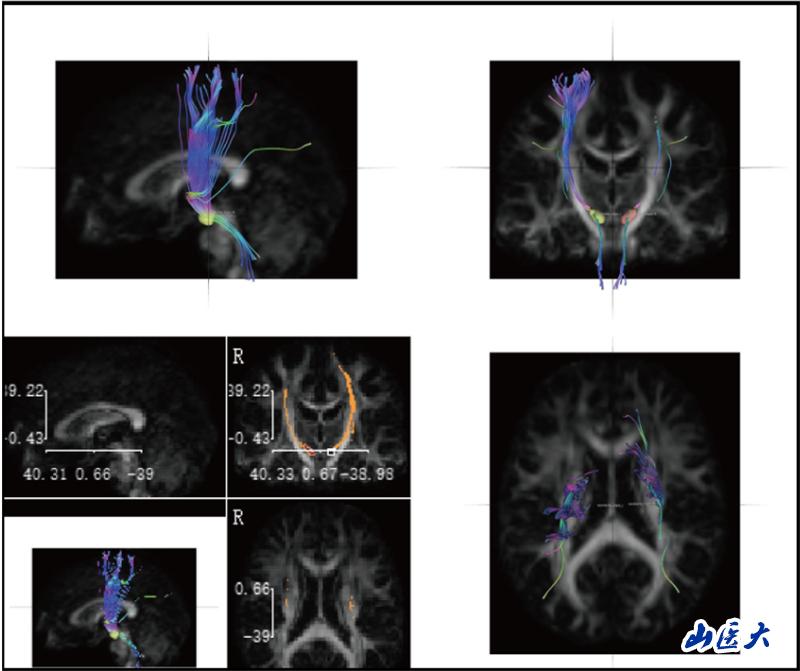

神经解剖学教学长期面临"结构隐匿性"与"空间复杂性"的双重挑战。传统的大体标本和平面模型难以展现纤维束、核团等微观结构的空间关系,易导致学生神经解剖结构认知困难。研究团队针对这一痛点,创造性引入前沿神经影像技术—DSI Studio纤维束成像系统。该技术通过对扩散磁共振成像(dMRI)数据分析,实现纤维路径智能追踪、三维动态重建及多维度交互可视化,构建起"影像解剖-病理对照-临床关联"的一体化数字教学体系。

研究团队创新性构建"理论-操作-临床"三阶整合教学模式,基于DSI Studio纤维束成像技术开展教学实践。选取38名低年级医学生为对象,通过整合人类连接组计划(HCP)标准脑数据库、帕金森病进展标志物计划(PPMI)及临床脑出血病例影像数据,建立"正常-病理"双模态教学资源库。此教学实践改革,不仅提升了学生神经解剖结构的空间理解力,并培养了学生从解剖结构认知到功能损伤解析的临床思维能力。

陆利教授团队长期致力于神经退行性疾病研究,此次将神经前沿进展转化为教学资源,实现了"科研数据教学化、教学过程科研化"的良性循环,使学生掌握解剖基础知识的同时,还可以智能化观察病理状态下的神经结构,为培养早期临床思维提供创新路径。